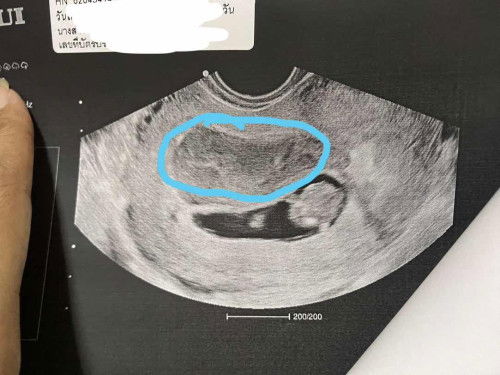

ขอสอบถามแม่ๆหน่อยค่ะ มีใครเคยเจอเหตุการณ์แบบนี้บ้างไหมค่ะ มีเลือดไหลทางช่องคลอดไปหา หมอมาแล้วหมอบอกมีเลือดอยู่ข้างๆถุงตั้งครรภ์ค่ะ ไปรอบแรกหมอบอกปกติไปมาเมื่อวานหมอเจอเลือดอยุ้ข้างถุงตั้งครรภ์มีแม่ๆคนไหนเป็นแล้วหายบ้างไหมค่ะ ที่วงสีฟ้าคือเลือดค่ะ ตอนนี้กังวลมากค่ะ#ขอบคุณสำหรับคำคอมเม้นล่วงหน้าค่ะ #ขอความคิดเห็นของคุณแม่หน่อยค่ะ #ขอคำแนะนำกับแม่ๆด้วยนะคะ